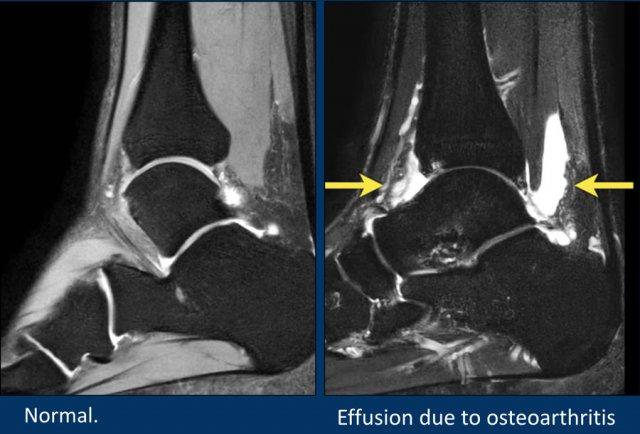

Tràn dịch khớp

Sau khi đánh giá hệ thống xương, hãy khảo sát các khớp để tìm dấu hiệu tràn dịch.

Hình ảnh bên trái cho thấy lượng dịch sinh lý bình thường trong khớp chày-sên, khớp sên-gót và túi hoạt dịch sau gót.

Hình ảnh bên phải cho thấy tràn dịch khớp lượng nhiều, là phản ứng đối với các tổn thương sụn-xương dưới sụn thoái hóa tại khớp chày-sên.

Dịch tràn có thể lan dọc theo bao gân cơ gấp dài ngón cái (FHL), do bao gân này thông thương với khoang khớp.